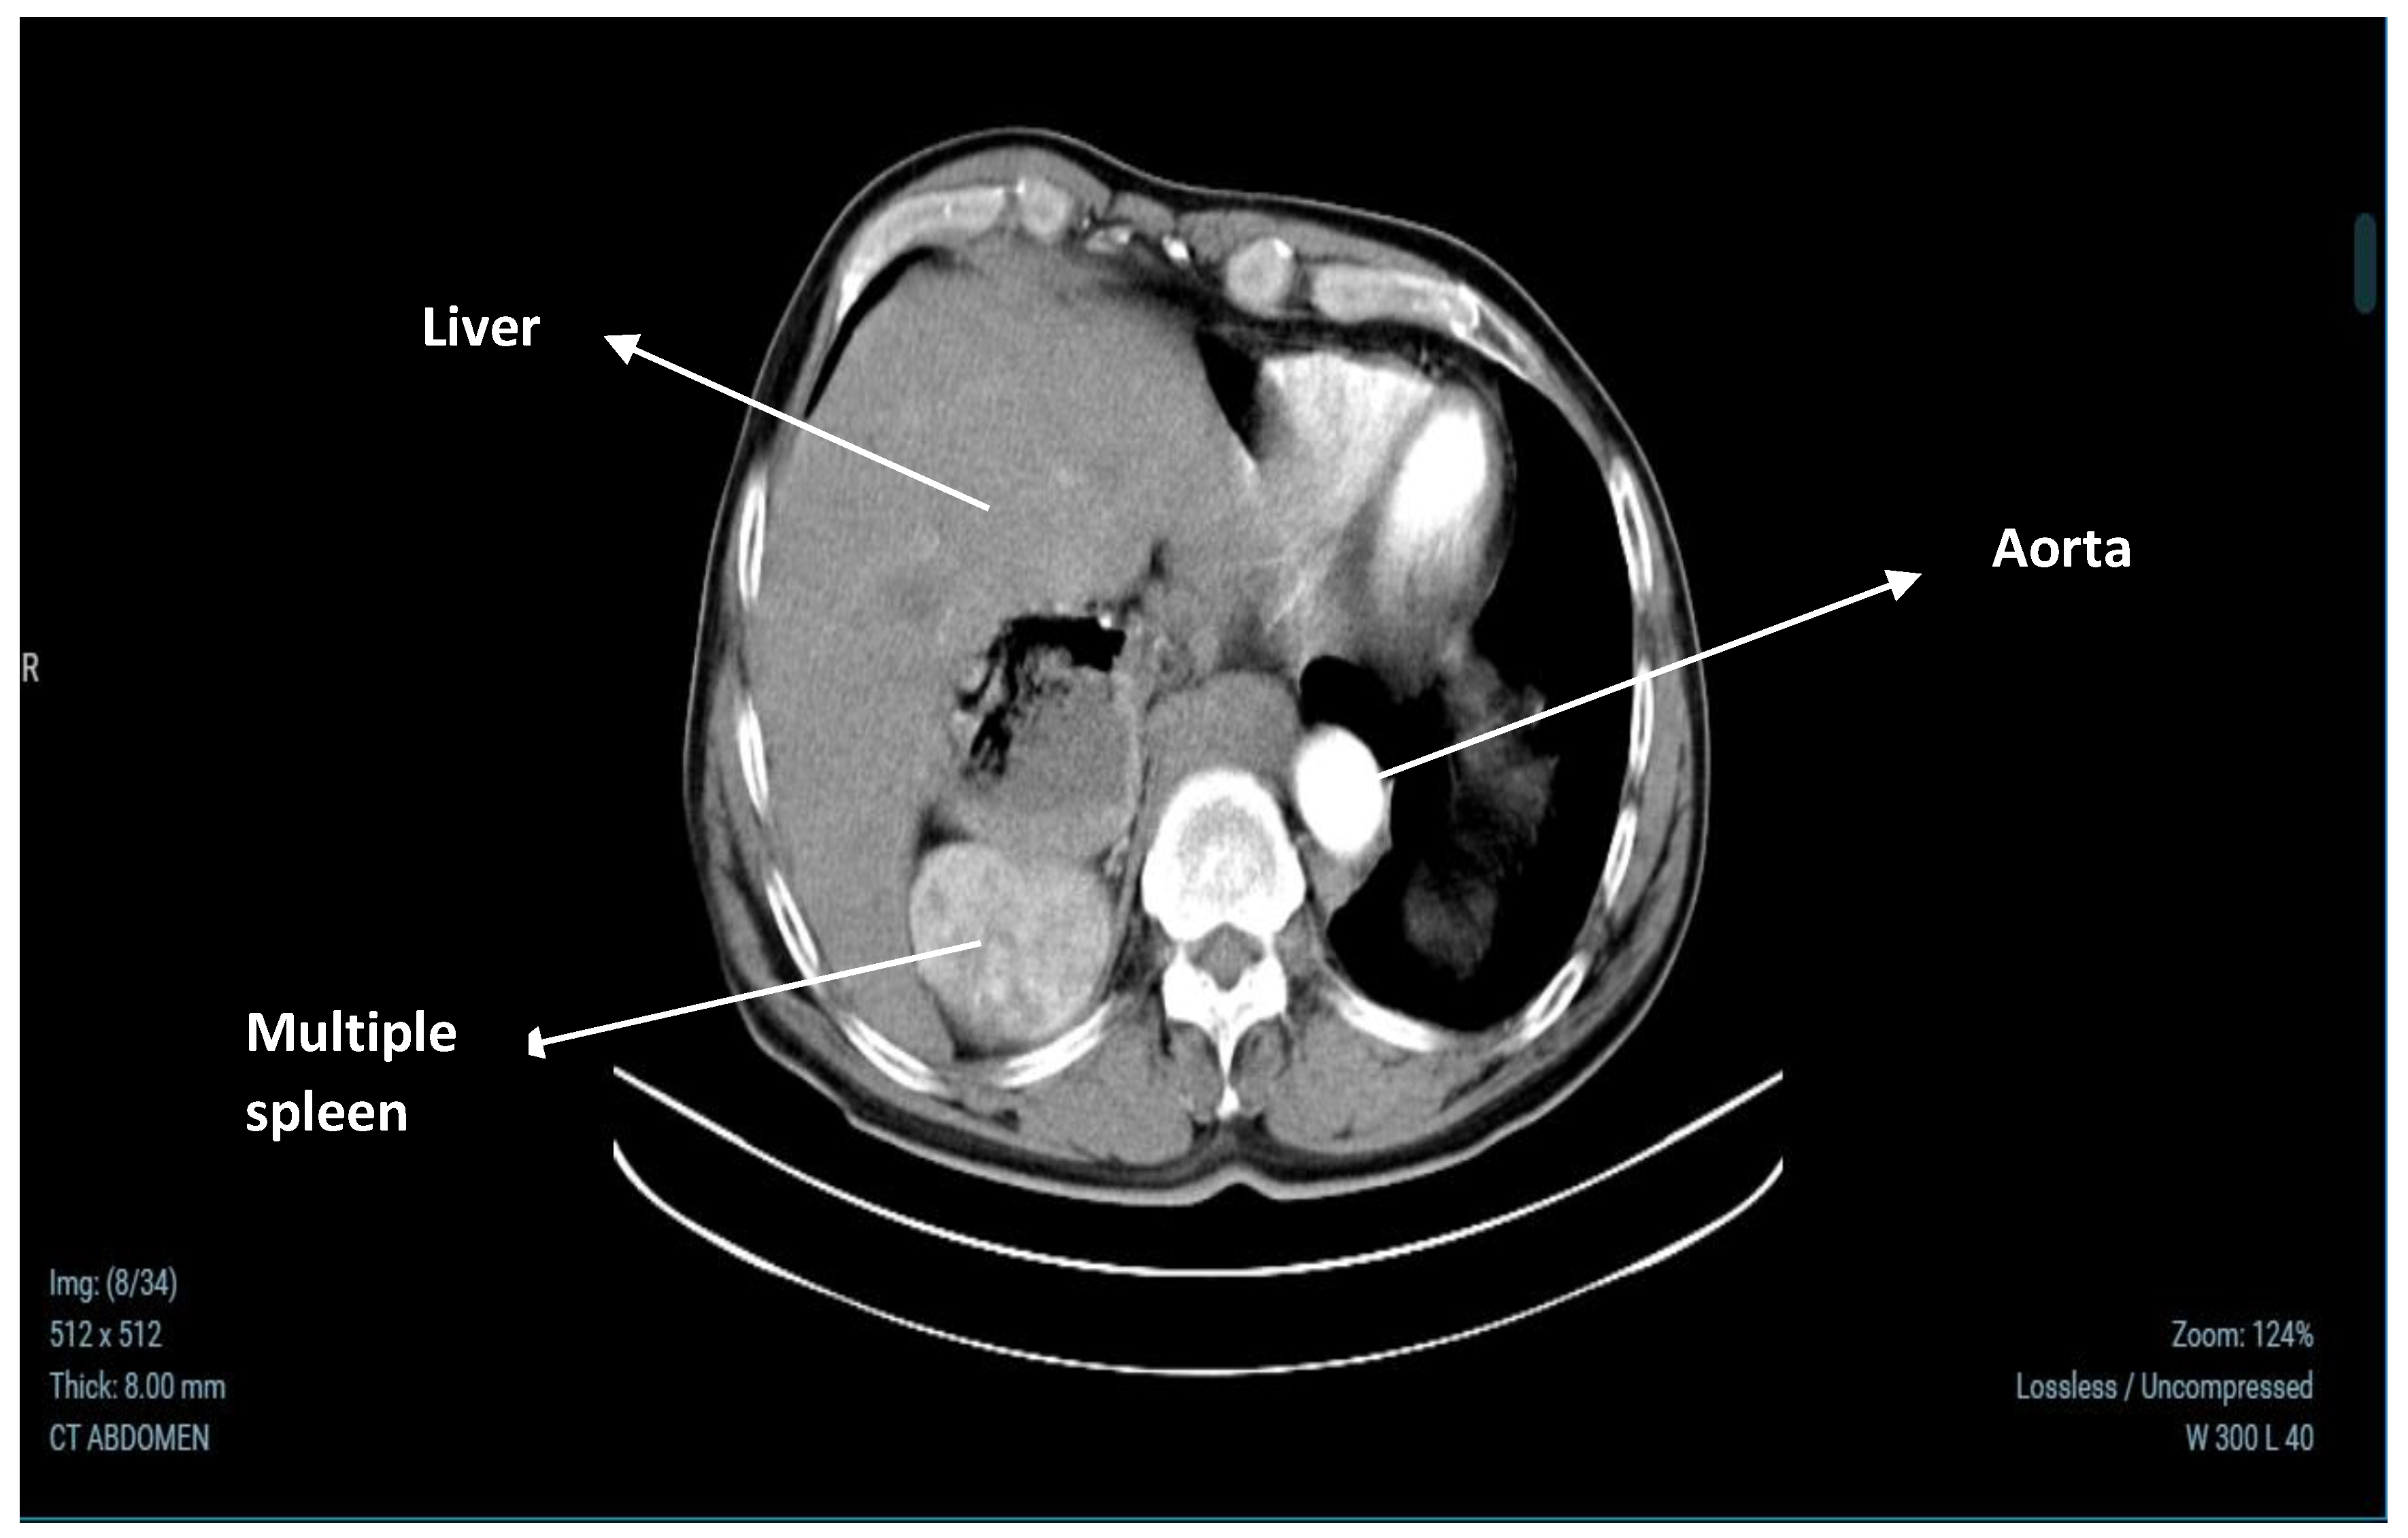

2.3. Abdominal CT Results

| Other Imaging Findings | CT scan revealed liver cysts and multiple splenic nodules; normal kidney size with cysts. |